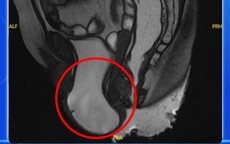

Người phụ nữ phát hiện bị sa sàn chậu từ dấu hiệu rất nhiều chị em Việt bỏ qua

Mẹ và bé - 11 giờ trướcGĐXH - Người phụ nữ bị sa sàn chậu có biểu hiện rối loạn tiểu tiện như tiểu khó, tiểu phải rặn và đôi lúc tiểu són, khiến cuộc sống thêm phần nặng nề...